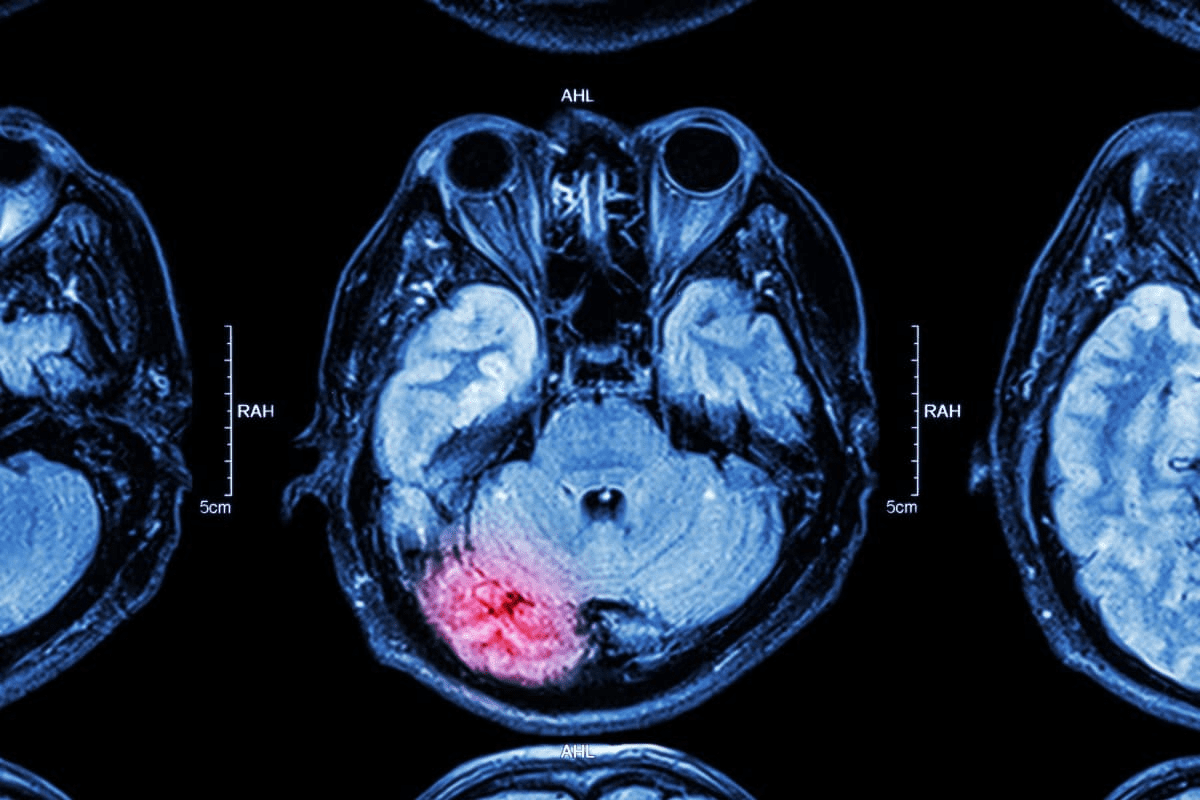

Identifying Cancer on Bone Scans: What to Look For

Understanding bone scans is key to spotting cancer. Doctors look for specific signs in the images. These signs can point to cancer.

Characteristic Patterns of Metastatic Disease

Metastatic disease shows unique patterns on bone scans. These patterns help tell if a condition is cancerous. Multiple focal areas of increased uptake are often seen in cancer.

Bright White Spots: What They Indicate

Bright white spots, or “hot spots,” on a bone scan mean increased bone activity. They can be benign or a sign of cancer metastasis. The intensity and spread of these spots are important.

Distribution Patterns That Suggest Malignancy

The way uptake is spread on a bone scan is key. Certain patterns, like diffuse uptake or uptake in many areas, hint at cancer. Below is a table showing common patterns and what they mean.